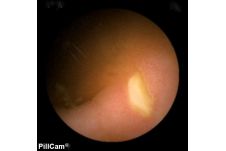

Der Dünndarm galt bis zur Einführung der sogenannten "Pillenkamera" als weitgehend uneinsehbarer Bereich. Dank einer innovativen Schluck-Kapsel mit Kamera und eigener Lichtquelle, die ohne eigenen Antrieb durch den Körper reist und währenddessen Bilder liefert, hat sich dies grundlegend geändert. Auch in der Klinik Mallersdorf wird diese Untersuchung durchgeführt, besonders zur Dünndarmdiagnostik.

Mit der Kapselendoskopie ist eine bildgebende Untersuchung des Dünndarms in einer für den Patienten schonender Weise möglich. Dabei wird eine Kapsel in Größe einer Penicillin-Kapsel geschluckt. Die integrierte Kamera nimmt während ihrer Reise durch den Magen-Darm-Trakt über einen Zeitraum von 8 Stunden Bilder auf und sendet sie an einen Rekorder. Die Kapsel wird dann auf natürlichem Wege ausgeschieden, die aufgezeichneten Bilder können mit einem speziellen Computerprogramm ausgewertet und befundet werden.

Die Kapselendoskopie wird besonders im Bereich des im Rahmen der Magen- und Darmspiegelung nicht einsehbaren Dünndarmbereichs verwendet. Sie hilft bei der Suche nach Blutungsquellen, chronisch entzündlichen Darmerkrankungen oder Tumoren.

Voraussetzung für eine Kapselendoskopie ist stets eine vorausgehende Magen- und Darmspiegelung. Sie ist also kein Ersatz, sondern eine Ergänzung für letztere.